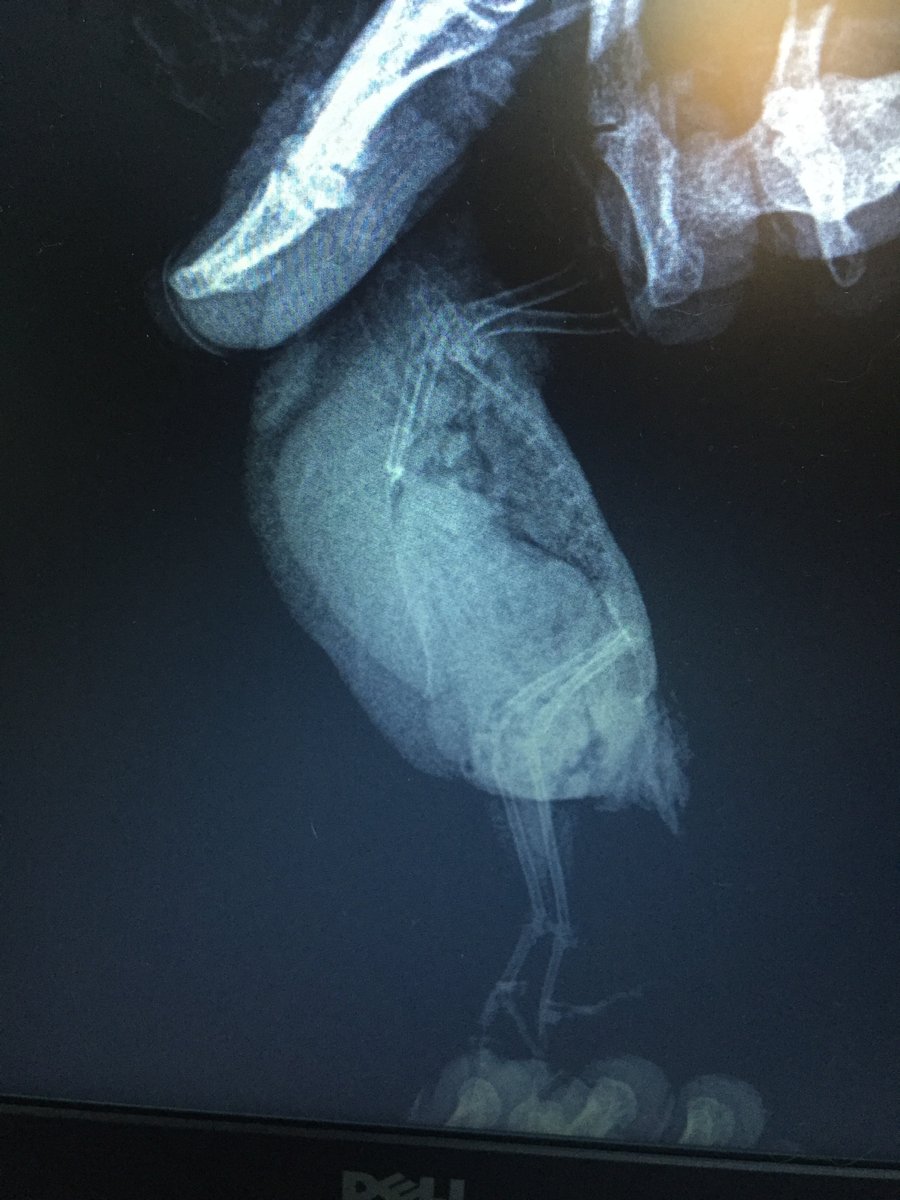

Сделали рентген и анализ помета.

По рентгену (см. приложение) – увеличен живот, печень.

Повторный рентген врач сказала можно сделать, но искать и определять у какого органа опухоль нет смысла, так как на лечение это не повлияет.

Фотографии сегодня сделала, насколько смогла четкие, трогать боюсь, он пищит, вырывается, посмотрите пожалуйста, фото рентгена от 05.06 прилагаю. Что это за опухоль? Чего ждать? Какая должна быть диета? Я сегодня где-то в ветке прочла, что морковь нельзя, а она у нас самая любимая. Из клетки не входит, со мной не общается. Я боюсь вытаскивать его в таком состоянии. Нужно ли его вытаскивать и провоцировать полеты? Как помочь?